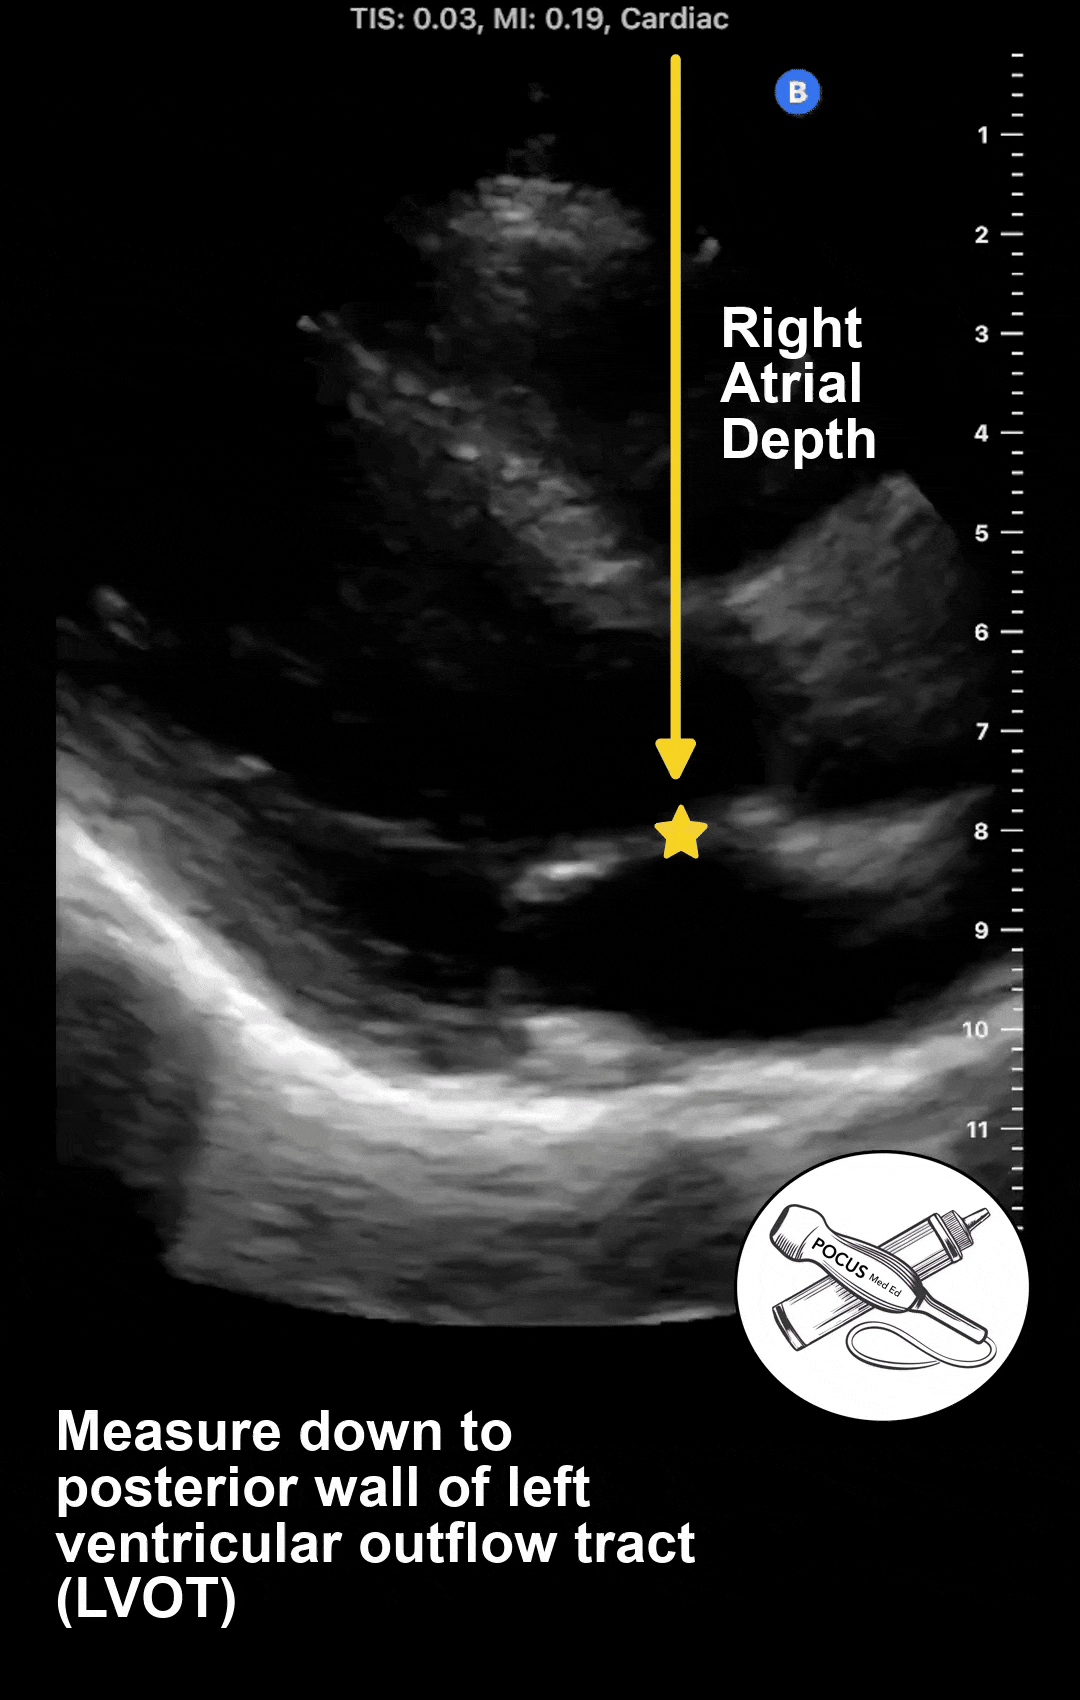

Step 2: Measure the right atrial depth using POCUS

In the traditional JVP exam, we are taught to add 5 centimeters to the measurement we get from step 1 to estimate the jugular venous pressure in centimeters of water. This is based on the assumption that the right atrium sits 5 centimeters below the sternum. However, we now know this is not true. The average depth is about 9 centimeters, but varies from 5 to 15 centimeters depending on the patient's body habitus. The only way to accurately measure this depth is with point-of-care ultrasound.

With the patient supine, acquire a parasternal long axis view of the heart. Then measure from the top of the screen down to the posterior wall of the left ventricular outflow tract. This sits in the same coronal plane as the center of the right atrium and can be used as a surrogate.

Since the height of a fluid column is equal to the pressure it exerts, adding these two measurements together will give you an estimated jugular venous pressure (JVP) in centimeters of water. This JVP estimate is synonymous with the right atrial pressure. A normal right atrial pressure is under 10 centimeters of water. To convert this to millimeters of mercury, which is the unit used in a right heart catheterization, multiply by 0.74. For more in-depth analysis and video tutorials, or to learn how to measure the right atrial pressure when JVD is absent, consider getting a copy of The POCUS Textbook.